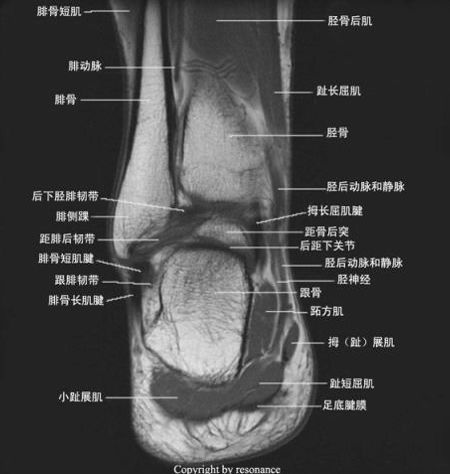

四、韧带撕裂

踝关节韧带:1.联合韧带;2.外侧副韧带;3.三角韧带;4.距跟韧带。

1.联合韧带:胫腓前韧带、胫腓后韧带、胫腓横韧带

2.外侧副韧带:距腓前韧带、距腓后韧带、跟腓韧带

跟腓韧带

距腓前韧带撕裂

距腓后韧带撕裂

跟腓韧带撕裂

3.三角韧带:胫距前韧带、胫距后韧带、胫跟韧带、胫舟韧带

三角韧带撕裂